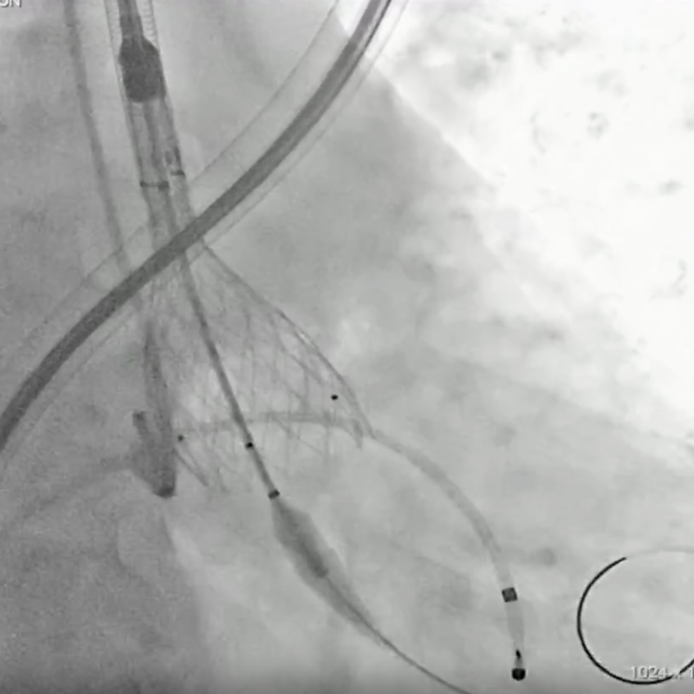

手术直播2:极重度钙化Type 1二叶瓣

本例患者78岁男性,重度AS并合并多瓣膜钙化,PGmax达112mmHg。CT评估提示Type-1二叶瓣,左右融合伴极重度钙化,延伸至升主动脉;瓣环与流出道均有钙化沉积,手术风险高。

经全面评估,最终拟经股入路,采用20/22 mm球囊预扩张后,植入VenusA-L 29mm瓣膜,备用32 mm瓣膜。术后造影与超声评估均显示瓣膜展开理想,无明显反流,手术成功。

小球囊预扩张

20mm球囊预扩张

双平面造影确认植入位置

释放完成

球囊后扩后,超声确认植入位置合适,形态满意,造影未见反流